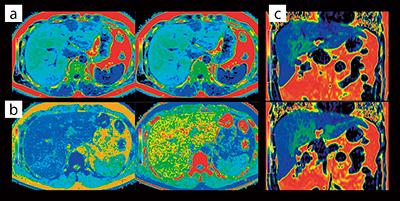

mDIXON Quantの臨床例として,

(1) fat fractionマップ,(2) R2*マップについて紹介する。

(1) 非アルコール性脂肪肝疾患(NAFLD)の診断には,肝生検をゴールドスタンダードとしているが,肝生検は侵襲性の高い検査であり,繰り返し検査することが難しい。そこで,非侵襲的な肝脂肪含有量(hepatic fat fraction:HFF)の定量方法としてmDIXON Quantが利用されている(図6 a)。

(2) ヘマクロマトーシスやヘモジデローシスといった組織の鉄沈着の程度を判断するためにR2*マップが利用されている(図6 b)。

図6 mDIXON Quant fat fractionマップとR2*マップ

脂肪肝におけるfat fractionマップ画像(a),R2*マップ画像(b),fat fractionマップ画像からMPR処理を行い冠状断で再構成した画像(c)を示す。各画像をカラー表示することで病変を視覚的にとらえやすくすることが可能である。